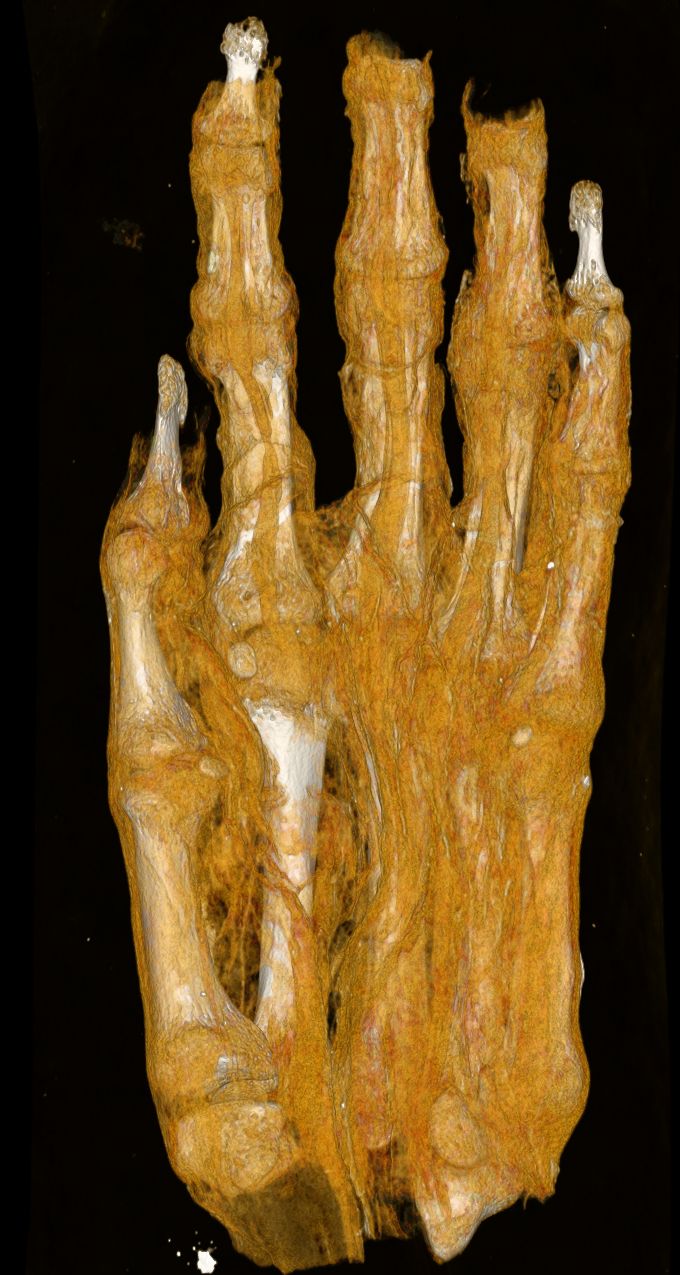

Különösen figyelemre méltó eredményt hozott egy, eddig csak múmiacsomagként értelmezett maradvány vizsgálata. A leletet a múzeumba kerülésekor – képalkotó vizsgálatok hiányában – fejként, később esetleg madármúmiaként határozták meg. Egy korábbi CT-vizsgálat azonban egyértelműen kimutatta, hogy egy felnőtt egyén lábfejéről van szó. A mostani képalkotó elemzés során arra keresik a választ, hogy a textilmaradványokból mennyire következtethetünk a mumifikálási technikára, valamint a mumifikált egyén életkorára, esetleges betegségeire. Az aktuális felvételeken ugyan is jól elkülöníthetők a különböző bandázsrétegek, valamint azok eltérő szerkezeti sajátosságai. Ezek további történeti és technológiai vizsgálatok alapját képezhetik. A maradvány egykor feltehetően egy teljes múmiához tartozott, azonban a test feldarabolásának ideje és oka jelenleg nem ismert.

A vizsgálatba bevont mumifikált kéz elemzése szintén fontos információkkal szolgálhat. A csontok mérete, fejlettsége és morfológiai jellemzői alapján a kutatók arra keresik a választ, hogy gyermek- vagy felnőttmaradványról van-e szó, valamint az egyén nemére és életkorára vonatkozó becslések is megfogalmazhatók lehetnek.